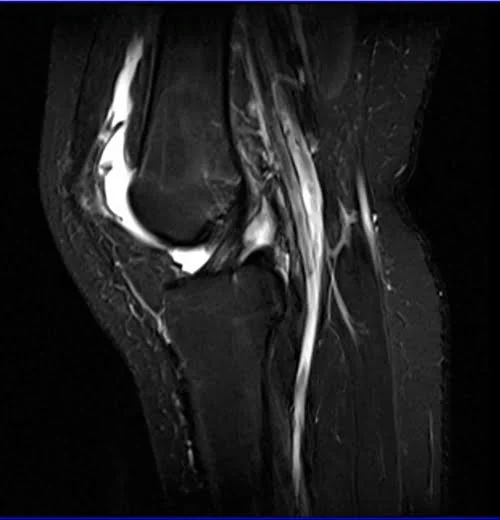

MRI knee sagittal stir 3 - MRI